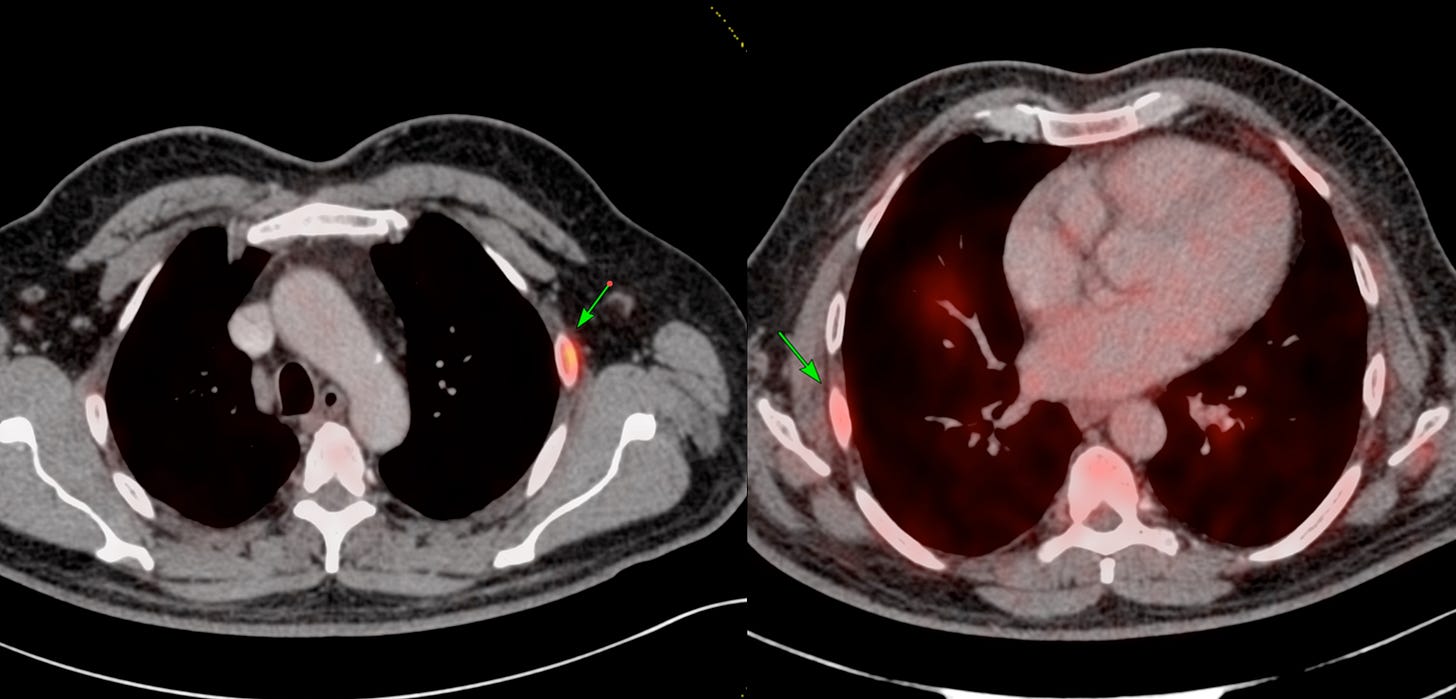

63-years old with Ca prostate had uptake on PSMA in the left 3rd rib anteriorly and right 6th rib posteriorly. The CT does not show any lesion there (Fig. 1).